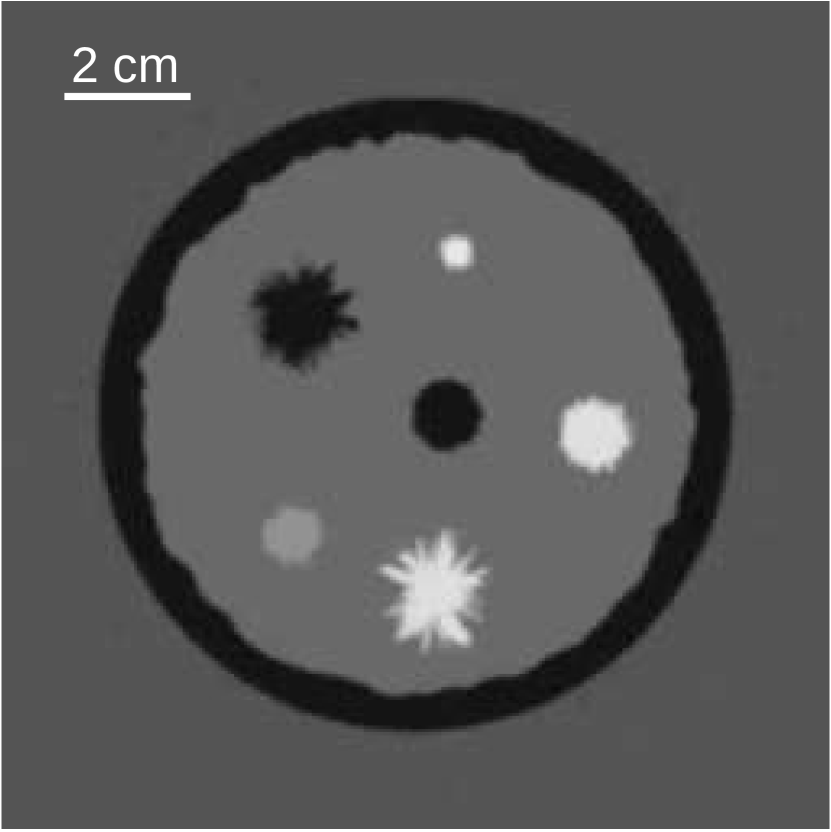

The numerical breast phantom had a radius of 49 mm and was composed of 8 structures representing adipose tissues, parenchymal breast tissues, cysts, benign tumors, and malignant tumors (See Fig. 2(a)). A detailed description of the numerical breast phantom can be found in [30]. A phantom consisting of two low-contrast bars was created for the bias-variance analysis (see Fig. 2(b)). The bars were placed far apart to minimize their influence on one another in the reconstructed images.

(a)

(b)

Figure 2: Sound speed distribution of (a) the numerical breast phantom and (b) the low-contrast two bar phantom employed in the bias-variance analysis, given in units of mm/μ𝜇\mus.